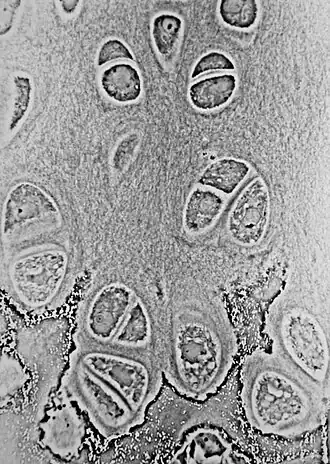

Light micrograph of undecalcified epiphyseal plate showing endochondral ossification: healthy chondrocytes (top) become degenerating ones (bottom), characteristically displaying a calcified extracellular matrix.

During endochondral ossification, five distinct zones can be seen at the light-microscope level:[3]

Zone of resting cartilage This zone contains normal, resting hyaline cartilage.

Zone of proliferation / cell columns In this zone, chondrocytes undergo rapid mitosis, forming distinctive looking columns.

Zone of maturation / hypertrophy In this zone, the chondrocytes undergo hypertrophy (become enlarged). Chondrocytes contain large amounts of glycogen and begin to secrete vascular endothelial growth factor to initiate vascular invasion.

Zone of calcification In this zone, chondrocytes are either dying or dead, leaving cavities that will later become invaded by bone-forming cells. Chondrocytes here die when they can no longer receive nutrients or eliminate wastes via diffusion. This is because the calcified matrix is much less hydrated than hyaline cartilage.

Zone of ossification Osteoprogenitor cells invade the area and differentiate into osteoblasts, which elaborate matrix that becomes calcified on the surface of calcified cartilage.